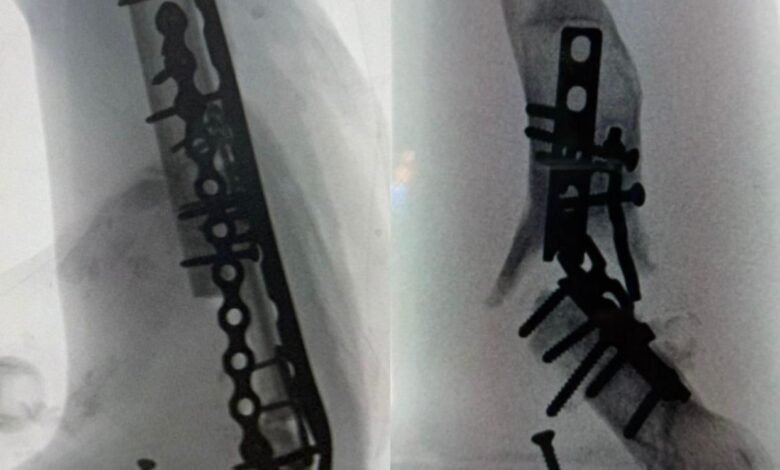

وفي تفاصيل الحالة، أوضحت المدينة أن الفريق الطبي في قسم جراحة العظام، بقيادة الدكتور بندر السهلي، والدكتور بسام العنزي، والدكتور حسين الياسين من وحدة جراحة الأطراف العلوية والمناظير، أجرى الفحوصات اللازمة التي كشفت عن إصابة شديدة في العضد الأيمن أدت إلى فقدان الحركة في المفصل. كما أظهرت الفحوصات وجود التهابات عضلية، وعدم التئام في العظم، وكسر في الشرائح المعدنية المثبتة للكسر، بالإضافة إلى نخر عظمي شديد، مما تسبب في تقييد حركة المفصل وظهور آلام مزمنة.

واستنادًا إلى نتائج الفحوصات، تم تجهيز عظم تعويضي وشرائح متخصصة للتعامل مع الحالة. وخضع المريض لعملية جراحية دقيقة استمرت أكثر من سبع ساعات، شملت إعادة بناء وترميم الجزء العظمي غير الملتئم، وتثبيت موقع الكسر، وتحرير المفصل لاستعادة حركته الطبيعية. وقد تكللت العملية بالنجاح، ولله الحمد، وتمكن المريض من العودة إلى منزله وبدء مرحلة التشافي.